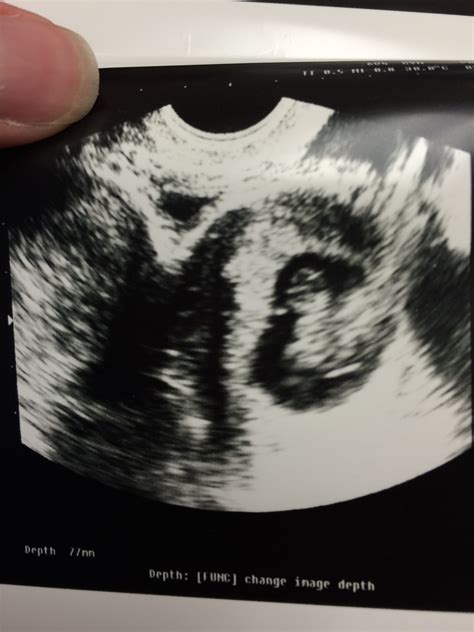

• Ultrasound Monitoring: Regular ultrasounds can help track the baby's position and detect any potential issues early.

Success Stories

Despite the challenges, many women with a bicornuate uterus have successfully carried their pregnancies to term and delivered healthy babies. These success stories highlight the importance of early diagnosis, specialized care, and emotional support. By working closely with healthcare providers and following recommended guidelines, women can increase their chances of a positive outcome.

One such success story is that of Sarah, who was diagnosed with a bicornuate uterus during her first pregnancy. Through regular prenatal check-ups, ultrasound monitoring, and progesterone supplements, Sarah was able to carry her pregnancy to term and deliver a healthy baby girl. Sarah's experience underscores the importance of early diagnosis and specialized care in managing a *bicornuate uterus pregnancy*.